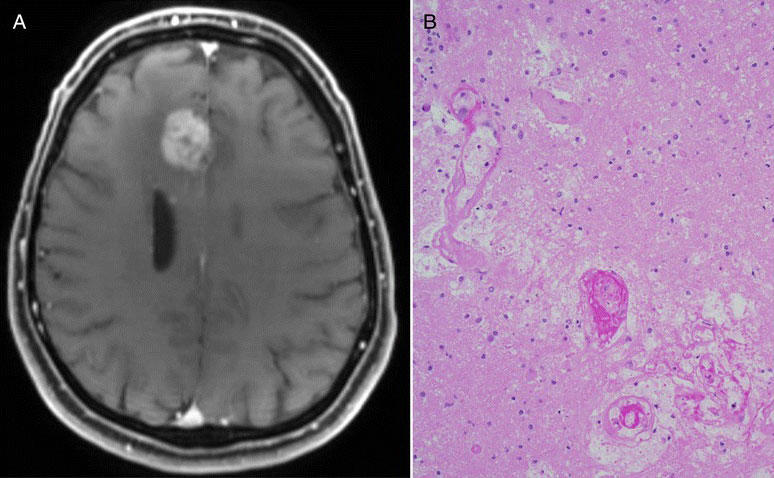

Even measuring whether an immunotherapy drug is working against glioblastoma tumors is difficult. Standard imaging techniques, such as MRI, that are used to assess whether tumors are growing or shrinking in response to treatment may not be sufficient in brain cancer, Dr. Gilbert explained.

Side-by-side images showing a brain MRI with a glioblastoma tumor (left) and  microscopic tissue section with pseudoprogression features (right).

An example of "pseudoprogression": imaging suggested a patient with glioblastoma had a growing tumor after treatment, but tumor sample analysis indicated the treatment did kill most of the tumor.

Credit: BMC Medicine December 2015. doi: 10.1186/s12916-015-0536-8. CC BY 4.0.

As several small studies have demonstrated, with these imaging methods, it’s very difficult to differentiate between tumors that are growing despite treatment and those encased by inflammation caused by an active immune response—a phenomenon known as pseudoprogression. In the latter case, treatment may be prematurely stopped in a patient whose tumors may actually be responding to the therapy.